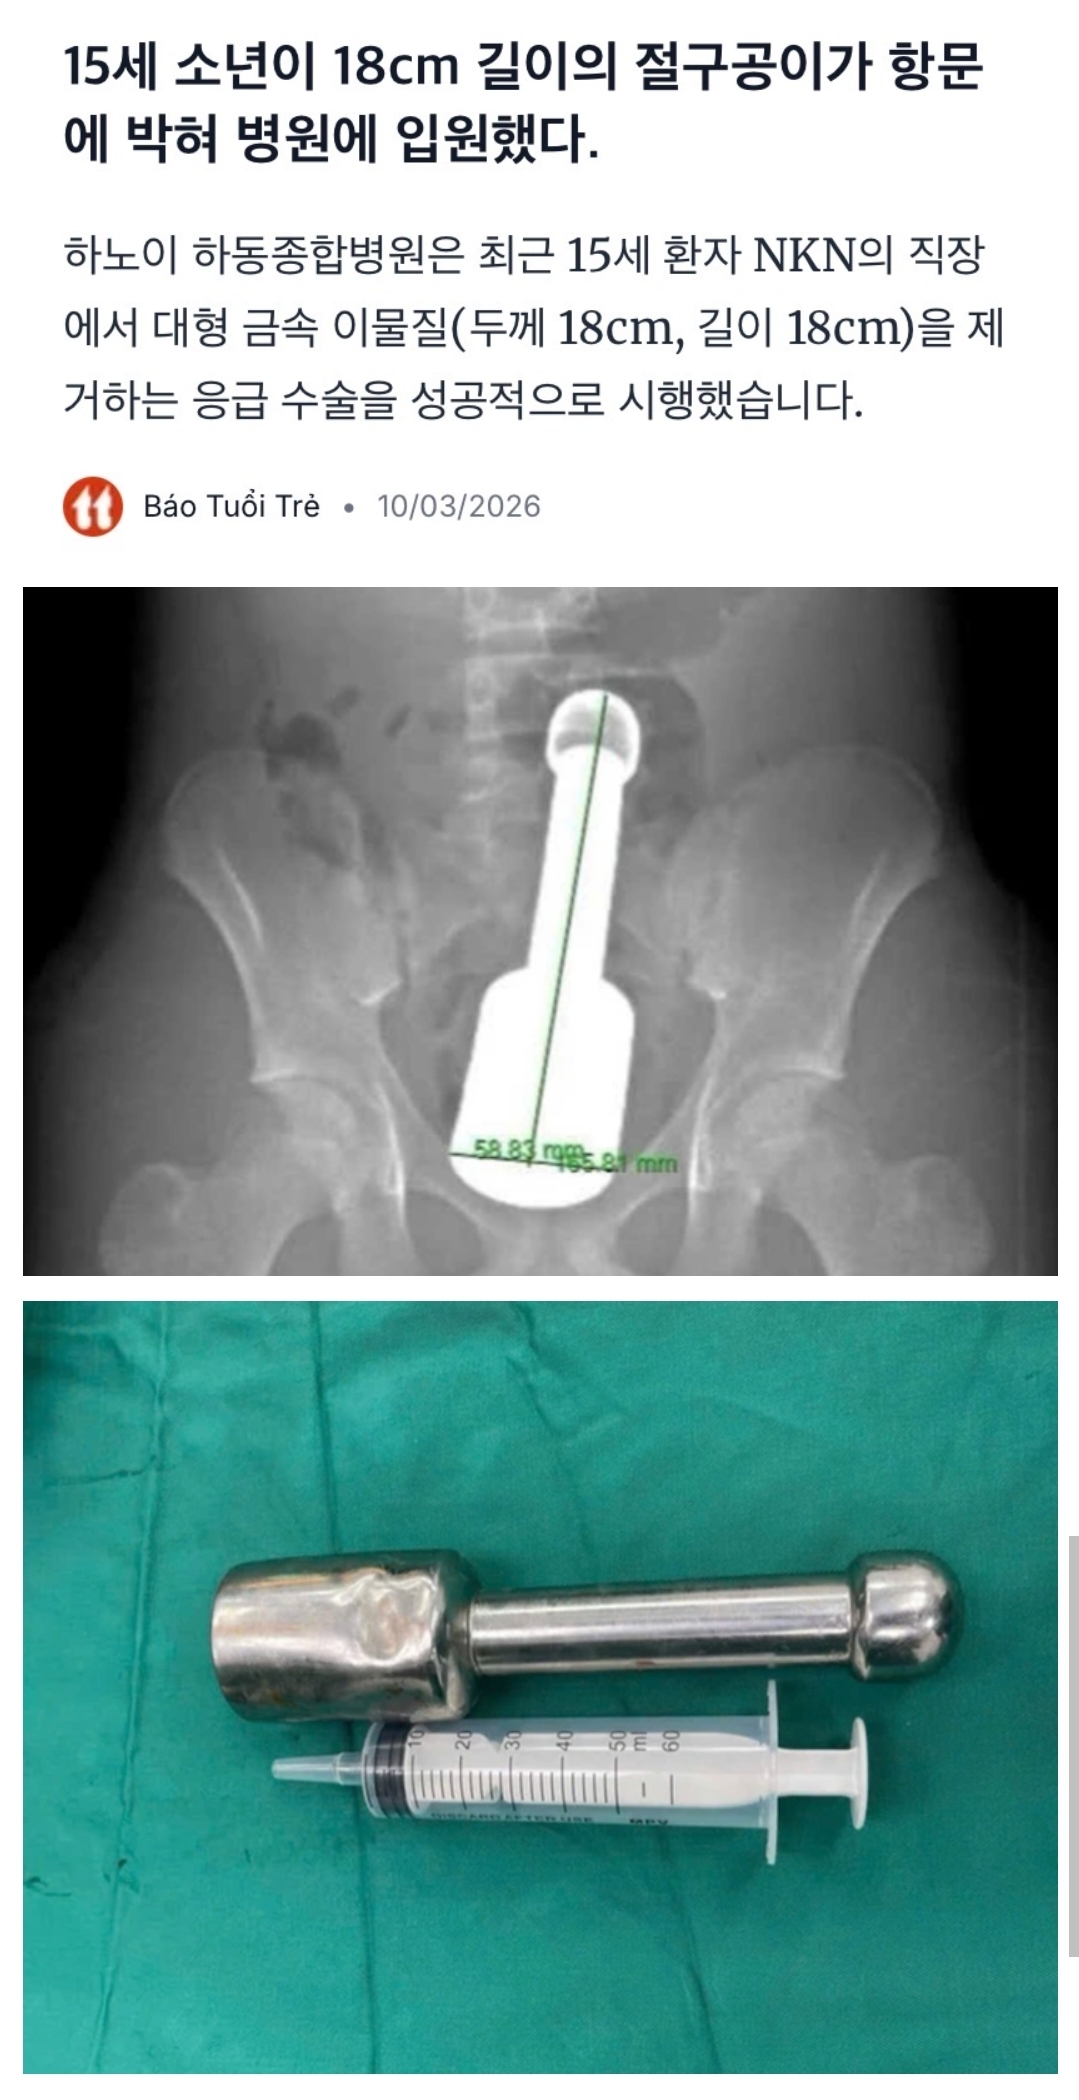

¾Æ Àú·±°É ÀÛ½ºÆ®·¦À̶ó°í ºÎ¸£´Â±¸³ª